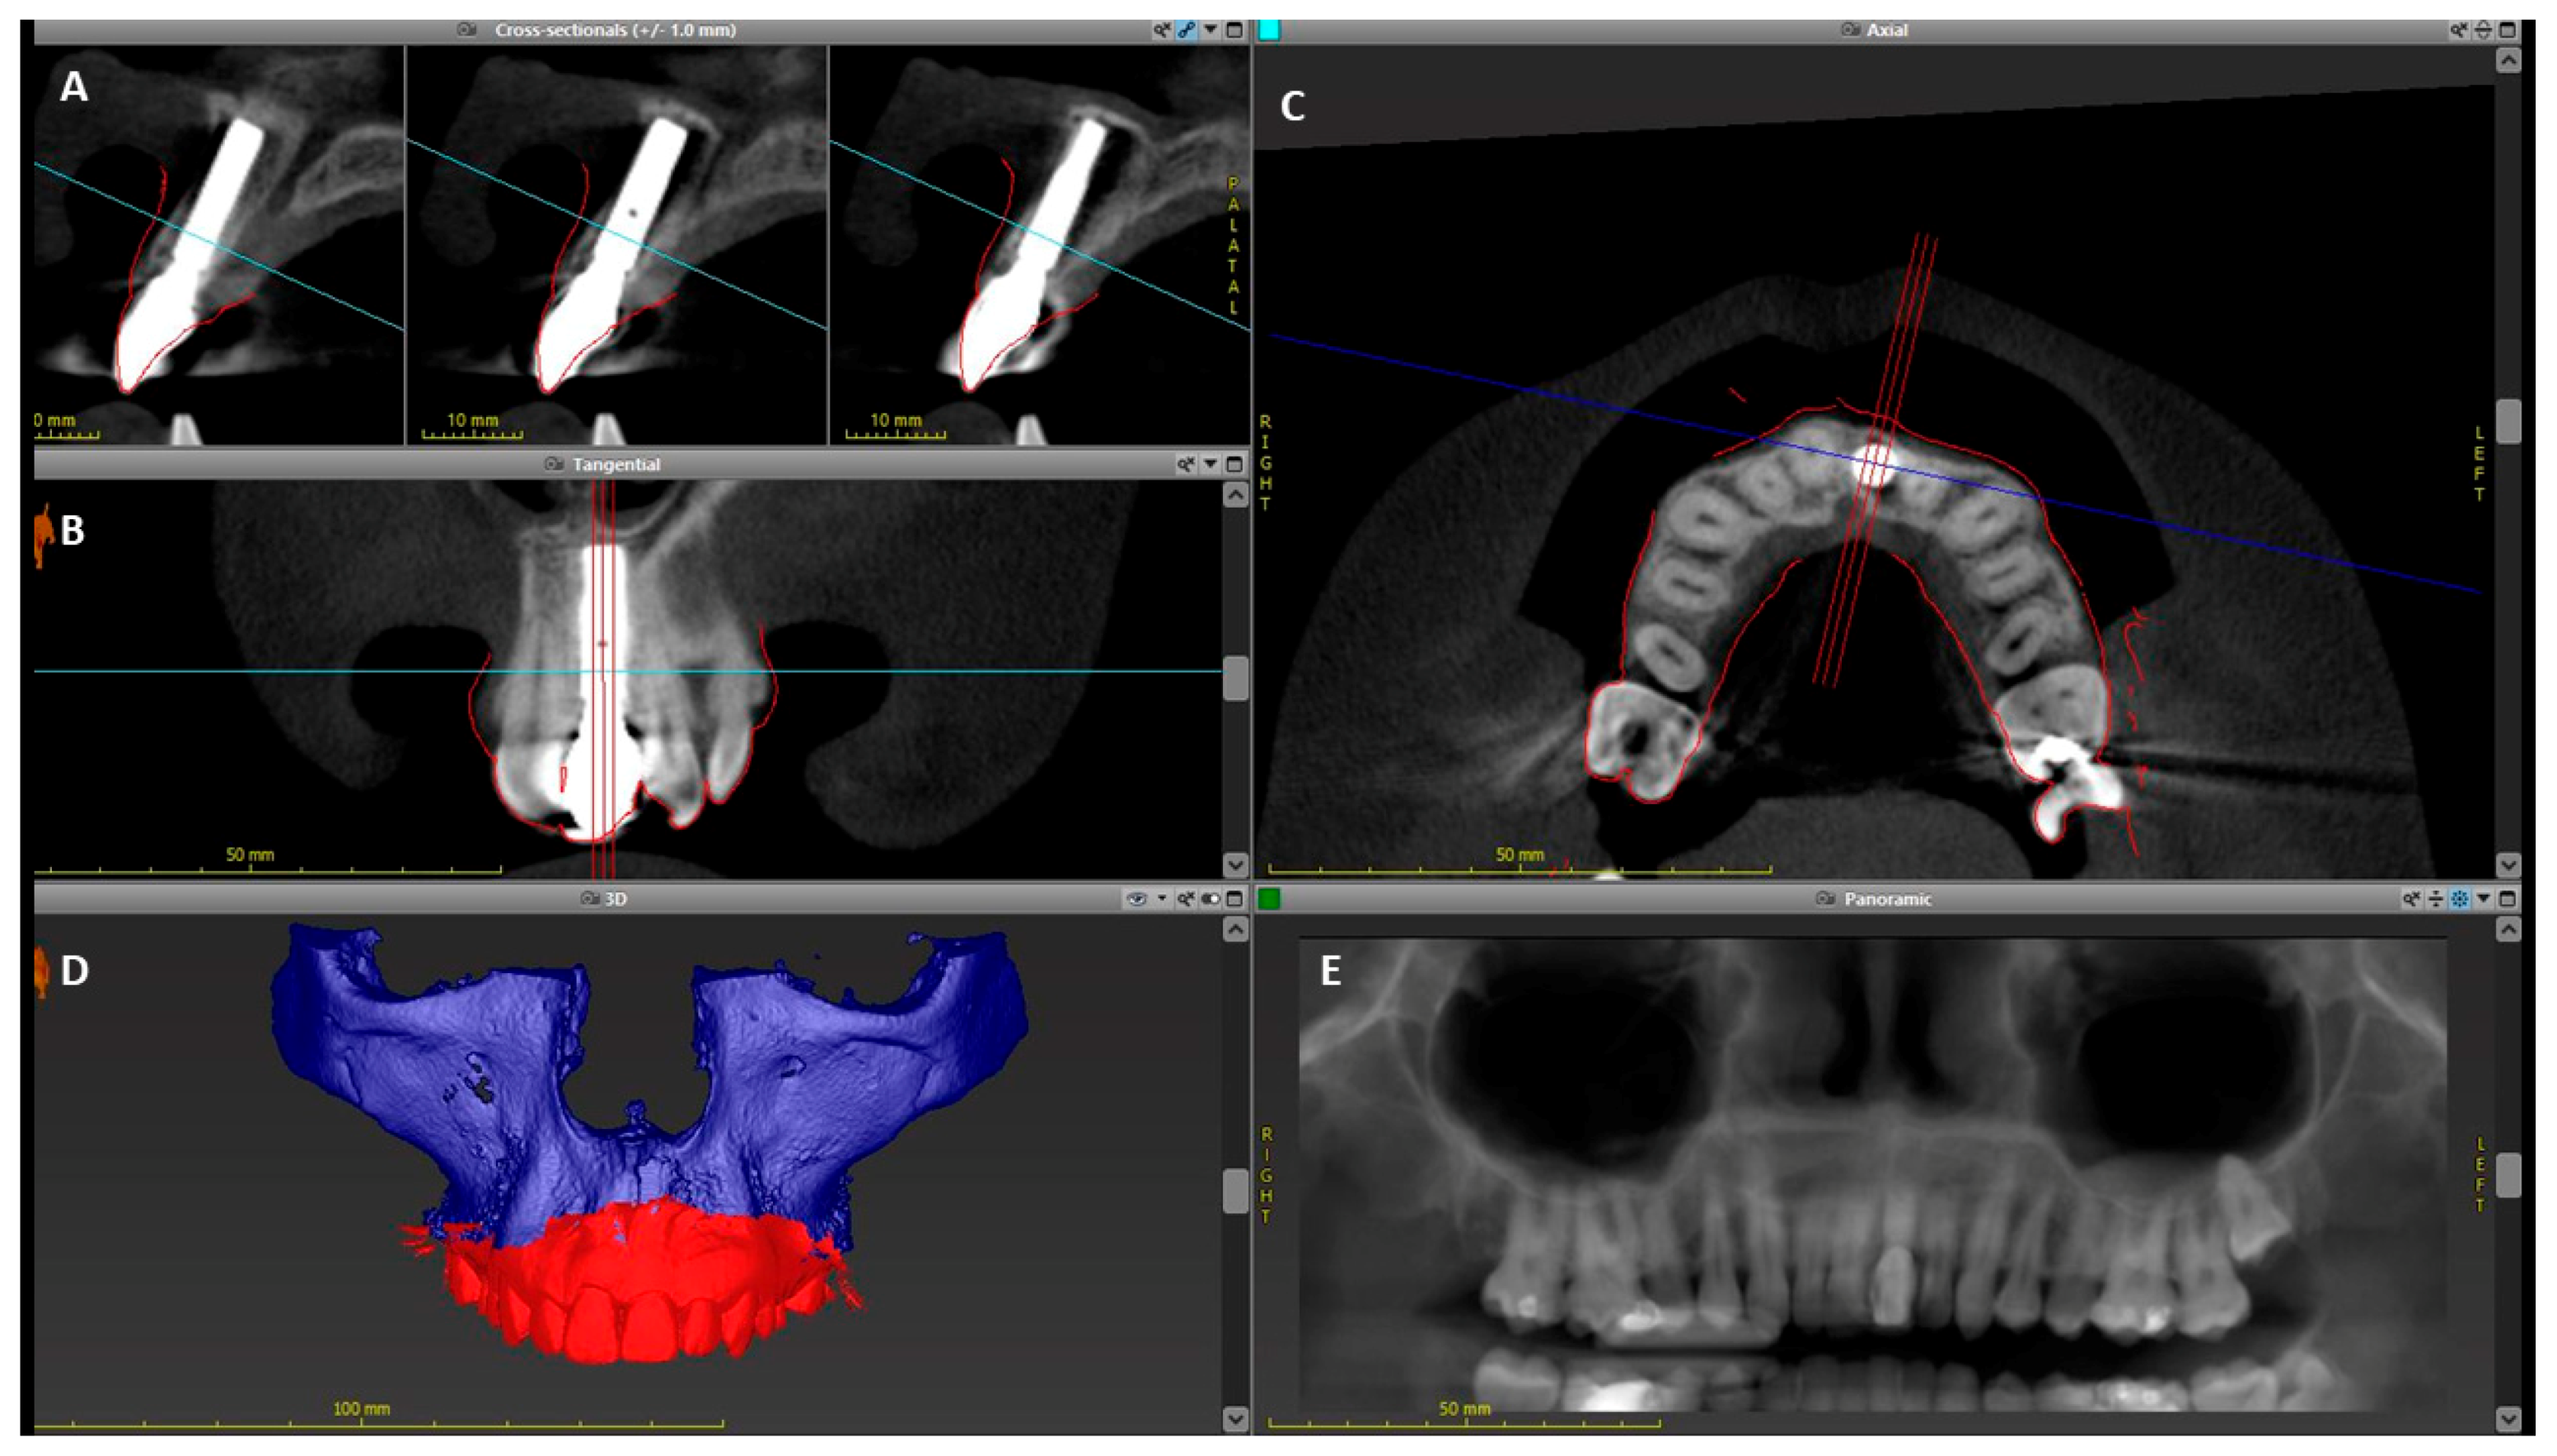

At the 10-year follow-up (T5), a CBCT scan as well as an intraoral digital scan (TRIOS, 3Shape, Copenhagen, Denmark) were done to evaluate the soft and hard tissues around the implant. Both scans were imported into an implant planning software (coDiagnostiX, Dental Wings, Montreal, QC, Canada). The intraoral scan was merged with the DICOM data from the CBCT in the software to evaluate the dimensions of the bone and soft tissues around the implant (Figure 4). After merging the intraoral and CBCT data in the software, an implant avatar with make and dimensions similar to the actual implant was imported and superimposed (Figure 5B). Two annotation lines were drawn through the center of the implant longitudinally and the implant platform horizontally. Horizontal measurements were made from the center of the implant to the outer level of bone and soft tissue at 1, 3, and 5 mm from the implant platform. Vertical measurements were made from the annotation line at the level of the implant platform to evaluate the height of the bone and soft tissue level above the implant (Figure 5C).

Figure 4.

Working screen for the coDiagnostiX software. (A) Implant in cross-sectional view, (B) Implant in tangential view, (C) Implant in axial view, (D) CBCT scan and intraoral digital scan from T5 imported and superimposed using coDiagnostiX software, (E) Reformatted panoramic view.

The results from the CBCT and intraoral scan superimposition were interpreted from the midfacial cross-section of the implant (Figure 5). The facial bone extended 2.1 mm above the implant shoulder in a coronal direction and the height of the soft tissue was 5.4 mm when measured from the implant shoulder. The mean thickness of facial bone and soft tissue around the implant was 1.45 and 1.3 mm, respectively (Table 2).